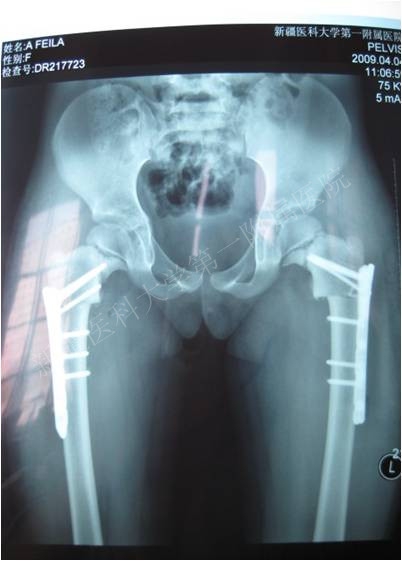

一典型患者术前术后X线片